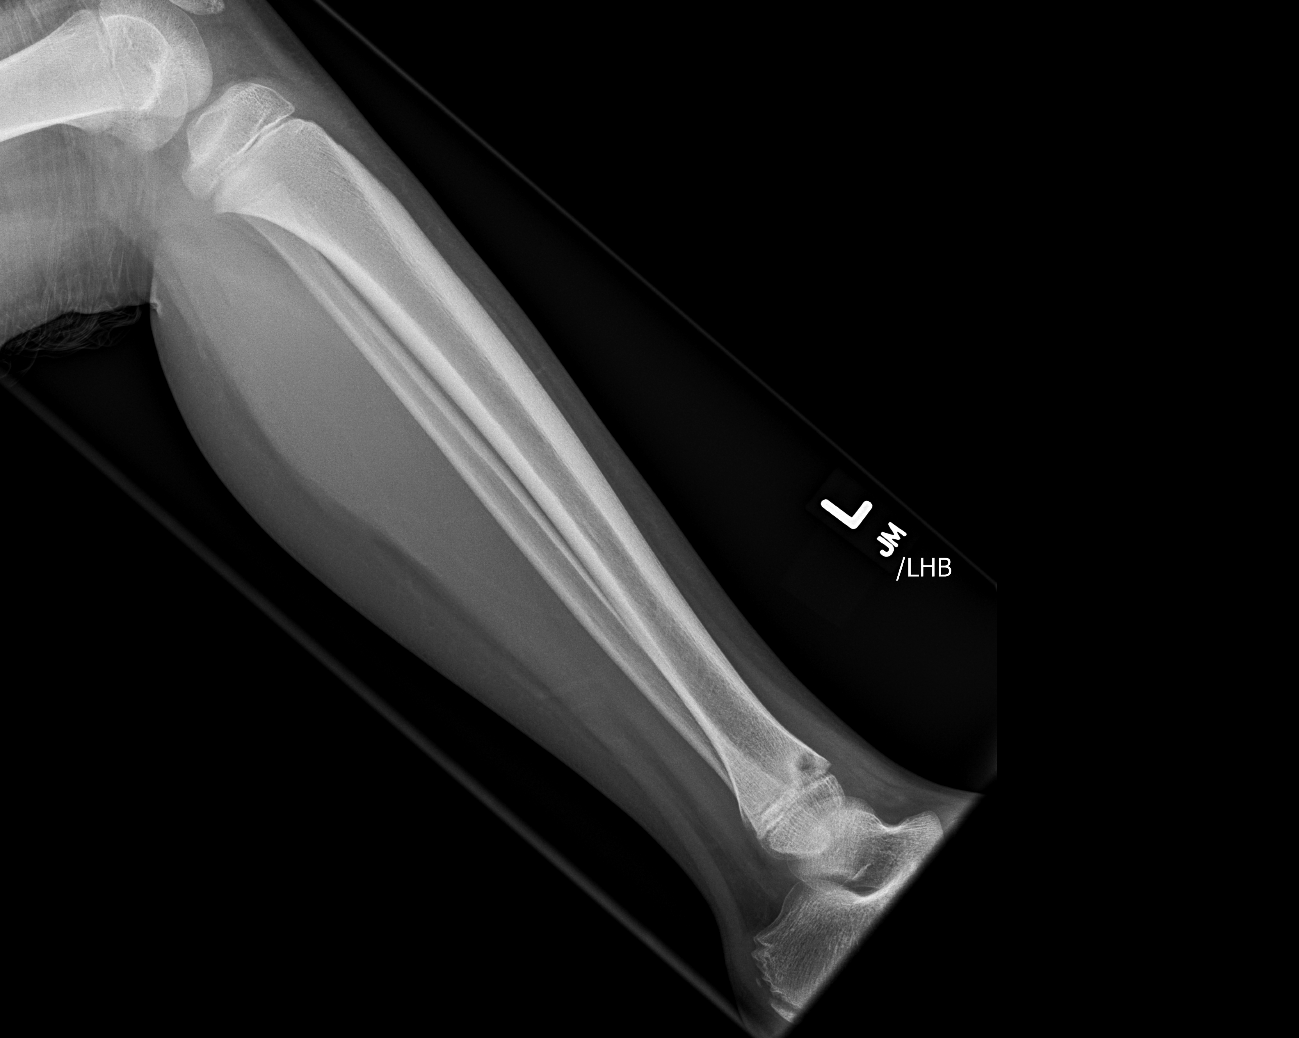

Findings

Bone

Growth plates, ossification centers, apophyses

Joints and alignment